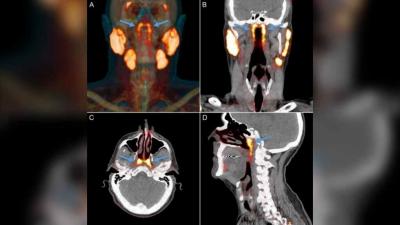

Researchers at the Netherlands Cancer Institute have identified a set of salivary glands deep in the upper part of the throat and have named them “tubarial salivary glands”.

The discovery may be important for cancer treatment. So far, this nasopharynx region — behind the nose — was not thought to host anything but microscopic, diffuse, salivary glands.

The newly discovered glands are about 1.5 inches (3.9 centimeters) in length on average and are located over a piece of cartilage called the torus tubarius, Livescience reported. According to the researchers, the glands probably lubricate and moisten the upper throat behind the nose and mouth.

The new organ was discovered while scientists were studying prostate cancer cells using PSMA PET-CT technology — a combination of CT scans and positron emission tomography (PET) — which is good in detecting salivary gland tissues. In this technique, a radioactive “tracer” is injected into the patient that binds to the protein PSMA, which is elevated in prostate cancer cells.